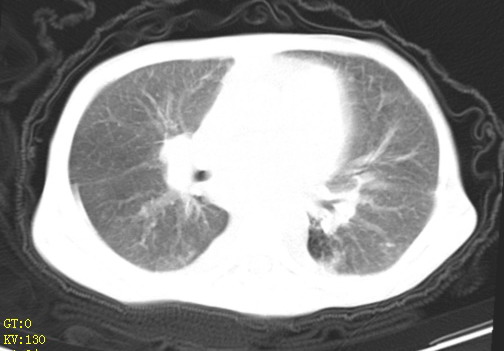

女,12岁,气促、咳嗽2天,3个月前查胸片示:两肺感染,急诊入院查ct,血常规等未检查。

左肺上叶改变考虑继发性肺结核,余双肺重症肺炎不排除h1n1。双侧胸腔少量积液。

双肺中下野不规则片絮状阴影,中外带明显,双侧胸腔少量积液,心影增大,心腔密度减低,隆突下及左侧气管旁见钙化淋巴结影,考虑双肺感染、心衰;建议结合临床除外h1n1并急性心衰,先心不能排除。

两肺多发片絮状模糊影,以下肺外带居多,内见支气管气像,纵膈窗未减影,两侧胸腔积液,心影增大,结合心超,支持重症肺炎,非常时期,甲型h1n1流感不排除。